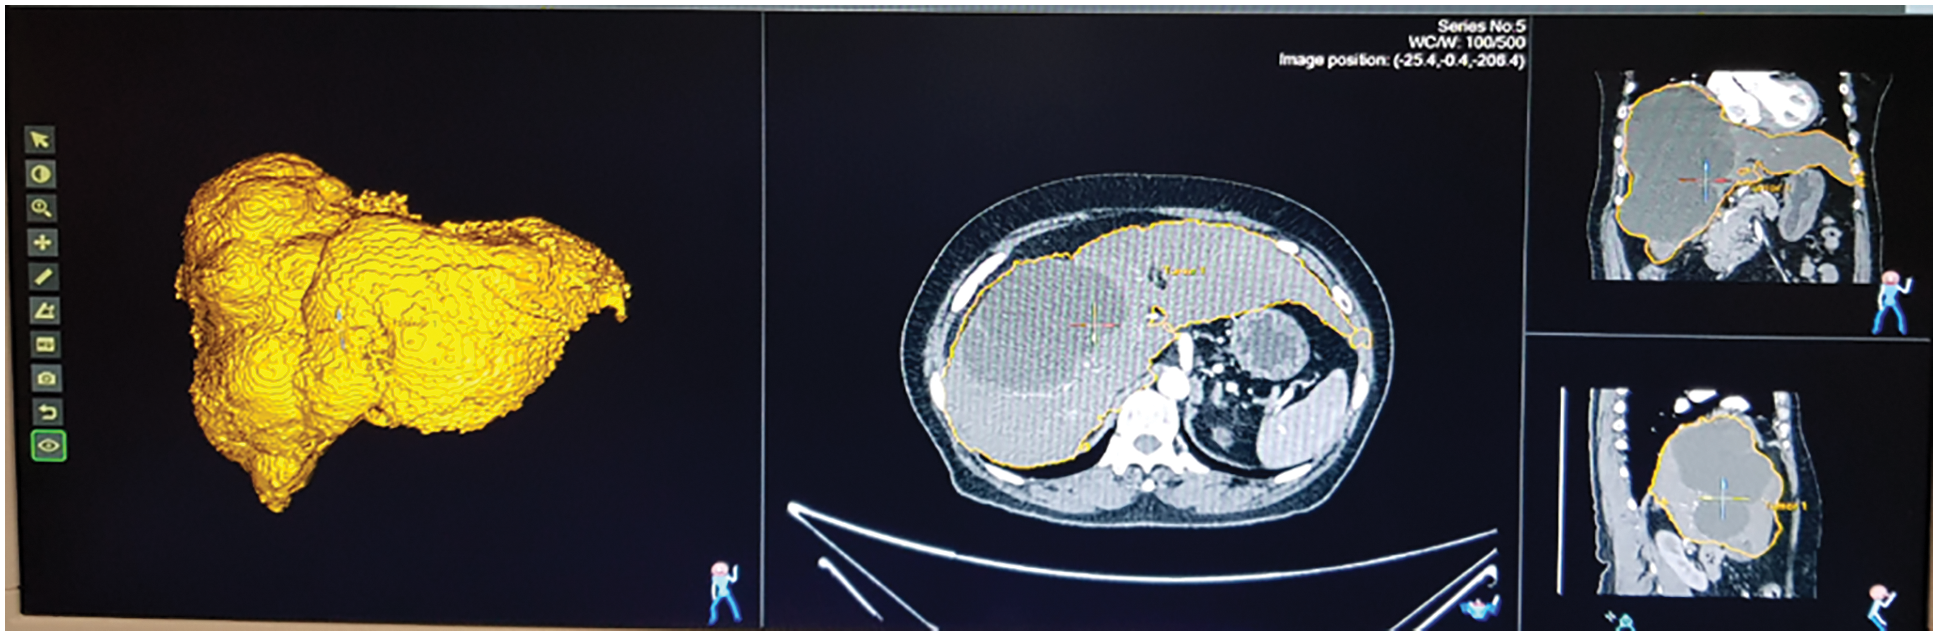

Fig. 13 shows the ultrasound value of medium fatty liver patient. The total liver volume is 1467 cc, right liver volume is 445.9 cc and left liver volume is 1021.88 cc. The medium fatty liver signal obtained from male patient age 70. Fig. 14 shows the ultrasound of mild fatty liver patient. The total liver volume is 961.86 cc, right liver volume is 365.93 cc and left liver volume is 595.33 cc. The mild fatty liver male patient at age 70. The signals from fatty liver are obtained from fatty liver sensor for sever mild and moderate fatty liver patients. The statistical parameters of the fatty liver signal from TQWT and the ultrasound lab values are correlated using gaussian regression modelling.

Figure 13: Ultrasound of medium fatty liver patient